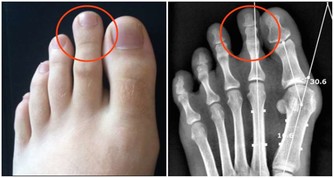

還有,抗生素在治療疾病的同時,或多或少帶有各種副作用,如果對它們的副作用不了解而濫用的話,後果將不堪設想。比如有的抗生素會影響聽力,甚至發生耳聾;有的抗生素對腎臟有損害;有的抗生素會引起過敏,使用前一定要做皮試,還有些抗生素使用後飲酒,會出現雙硫崙樣反應等等,因而在選擇時記得千萬要慎重。